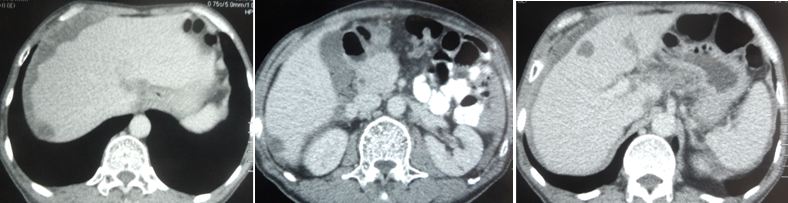

Wongson underwent an operation to remove the tumour in his colon in April 2018. The pathology report confirmed cancer – adenocarcinoma, pT4N1Mx. One of the two lymph nodes was affected. A CT scan on 9 May 2018, showed the cancer had spread to his liver.

A CT scan on 5 September 2018 showed that the tumour in his liver had shrunk from 2.49 cm to 2.06 cm. But it did not go away.

CT scan on 29 October 2019 showed:

- Mild ascites around the liver.

- Multiple cyst in both lobes of liver.

- Fractured compression at L4 vertebrae.